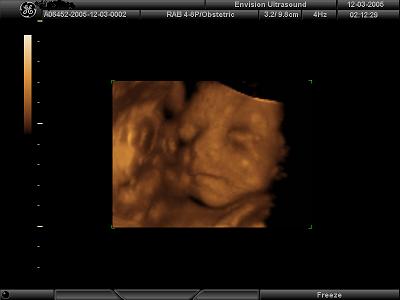

4D Ultrasound pics

We went to Envision in NJ yesterday to get our 4D ultrasound done for our 7 year wedding anniversary. It was the best gift we have ever given to each other!! Our little girl looks just like daddy but has mommys one dimple on her left cheek She is so beautiful and was playing with her umbilical cord the whole time trying to shove it in her little mouth. It was so fun to watch!! I would highly recommend getting it done. I posted my 4 fave pics out of 35 that we came home with and a lovely DVD set to music. Image Attachment(s):